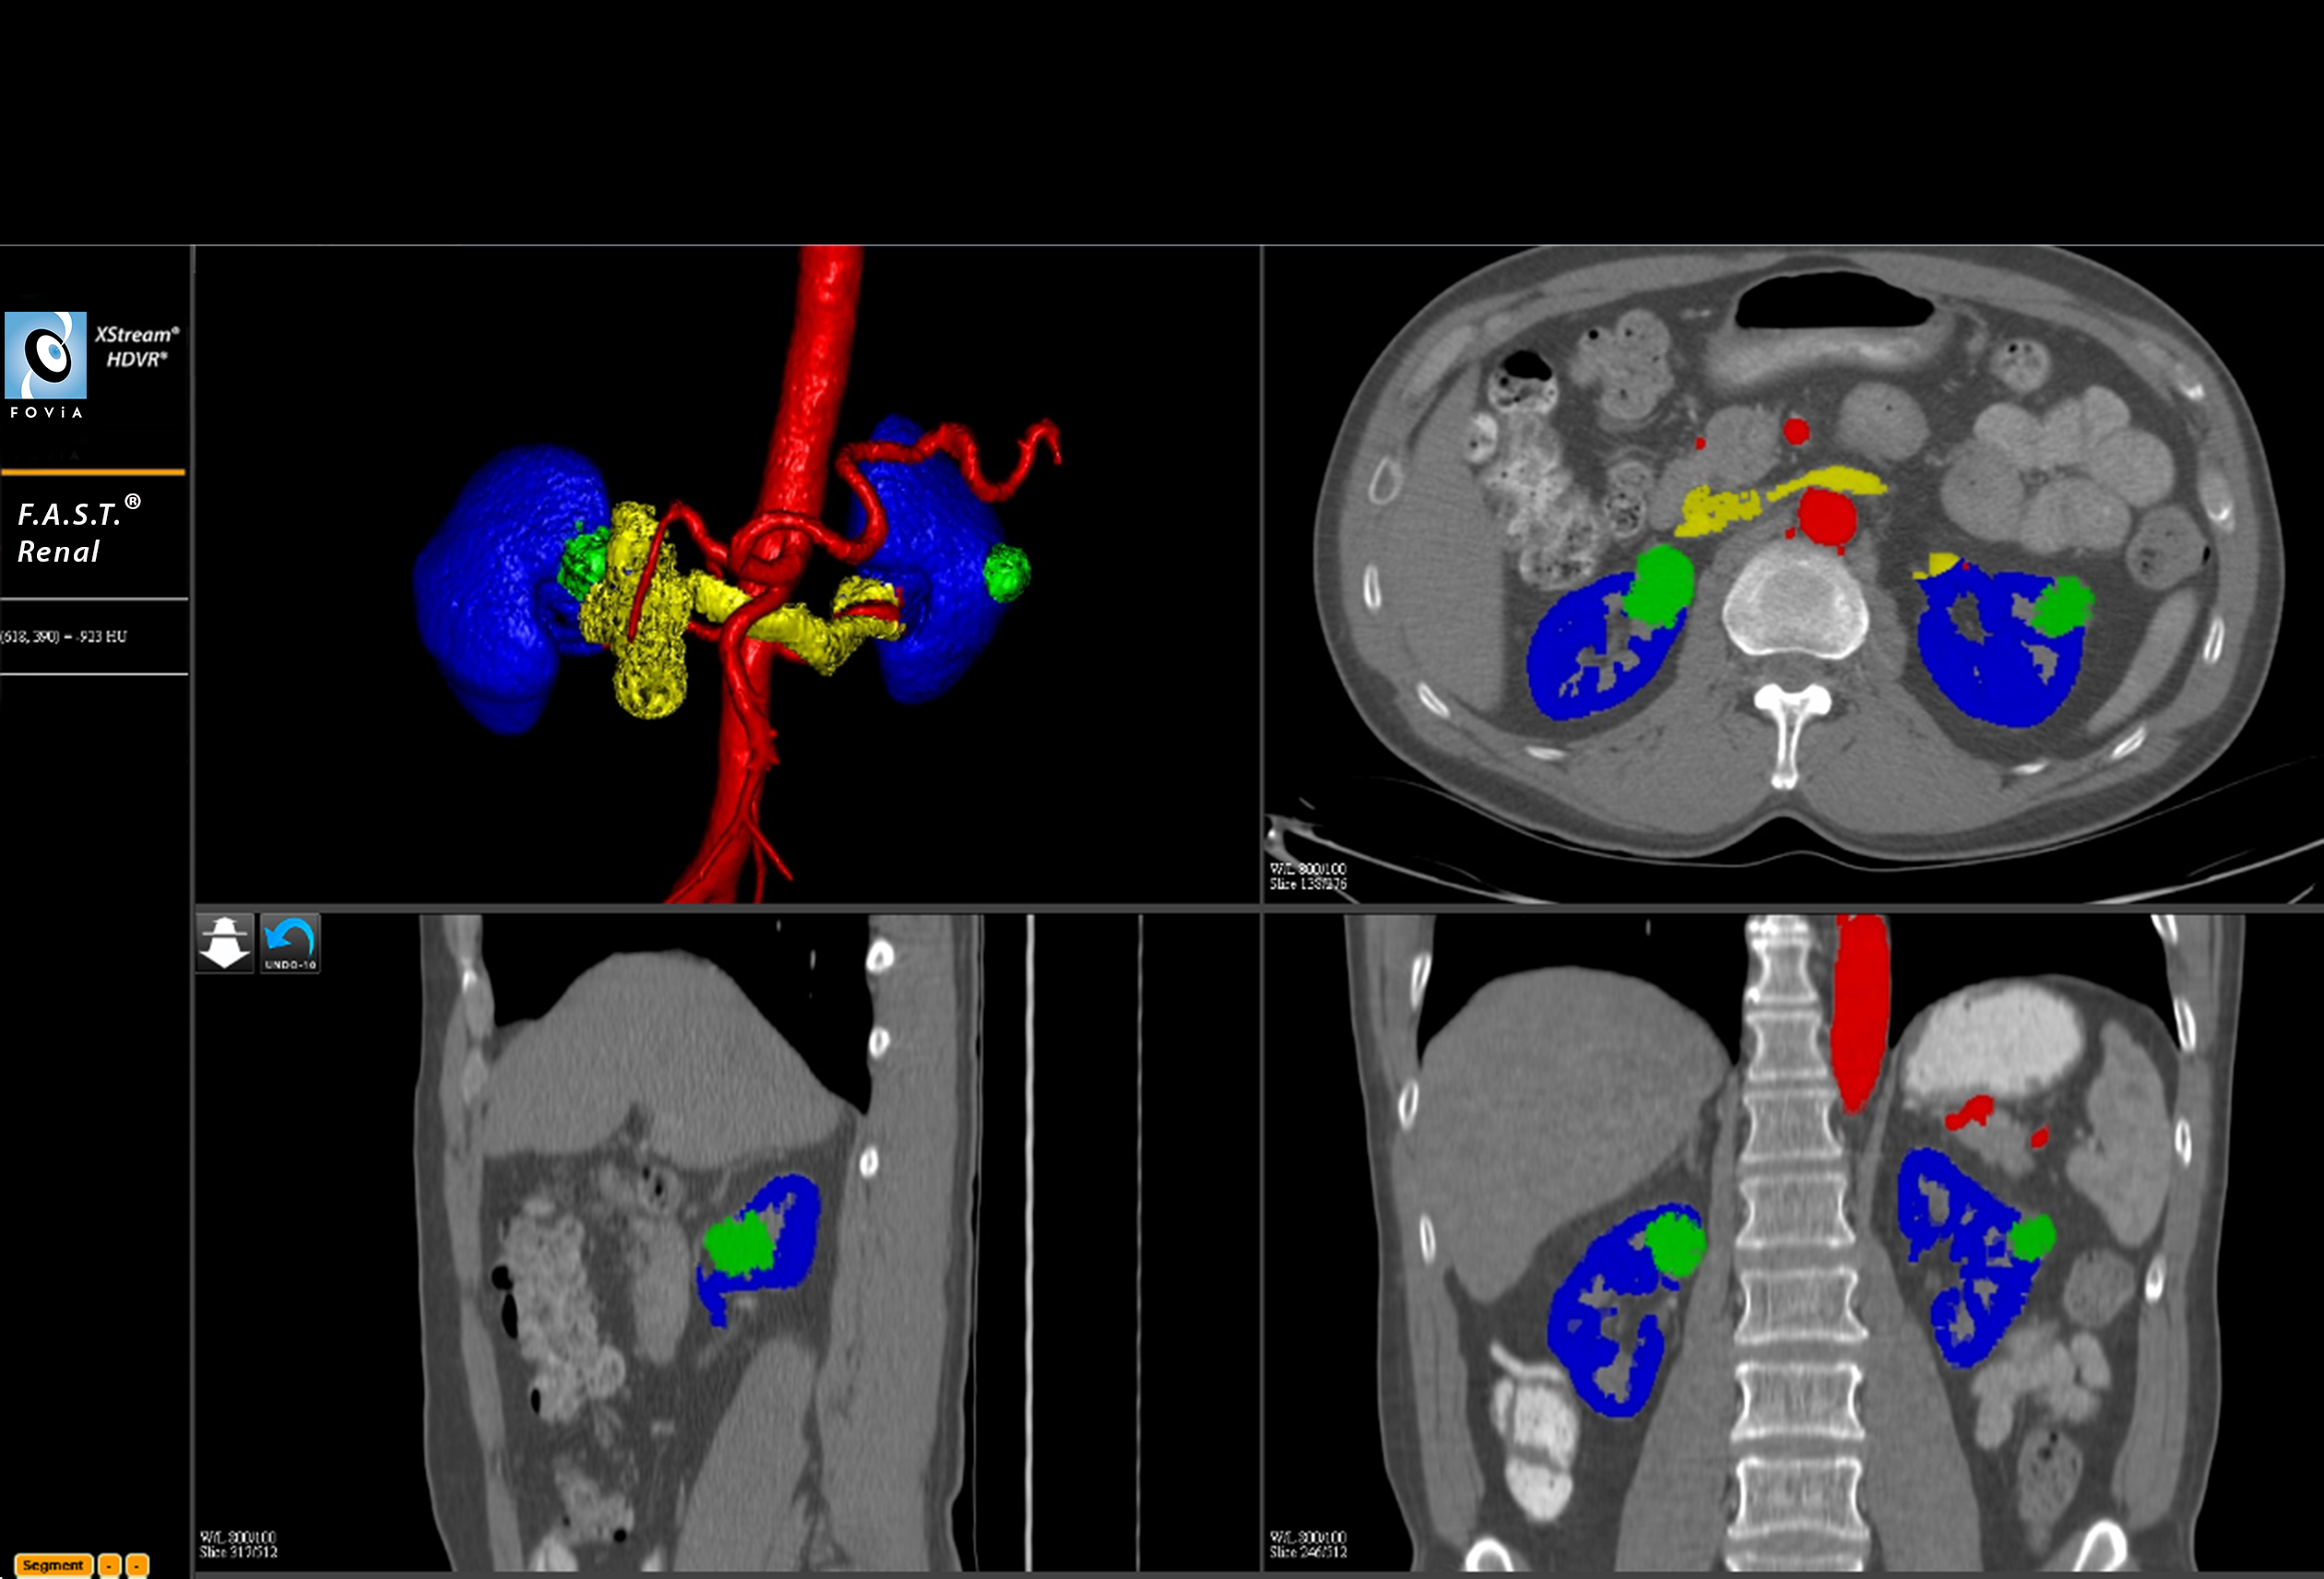

F.A.S.T. Renal Workflow

F.A.S.T. Renal Workflow